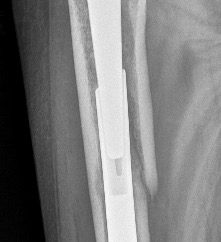

> Добрый день. Прооперировали, все хорошо. Канал рассверлили до 16, стержень

> 15,2. Поднимать больше ножку нестал, сделал одинаковые ноги. Всем спасибо,

> стержень подошел, сел как "родной".

​Посмотрел не на телефоне. Село все-таки глубоковато. Хорошо - как-то вот

так, см. приложение.

Надо обратить на это внимание, и не сдвигать "систему координат". ​

Не надо забывать, что может проседать и потом, и когда до дна приемной

гильзы считанные мм, это может привести к формированию зоны концентрации

нагрузок и перелому гвоздя, что недавно в Москве пронаблюдали!